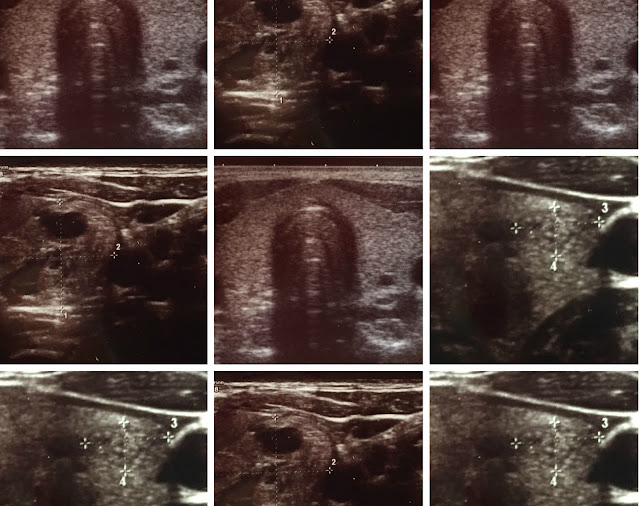

Jak wyglądają owe zmiany? Bardzo różnie- w języku medycznym mogą być hypo-, hyper- lub normoechogeniczne, lite albo płynowe, ze zwapnieniami, otoczką, mieszane, również unaczynienie guzków ma kilka typów… Może być jedna zmiana albo wiele. Te określenia informują nas o ich charakterze, oraz ewentualnym ryzyku złośliwości. Wspominałam o tym już tutaj.